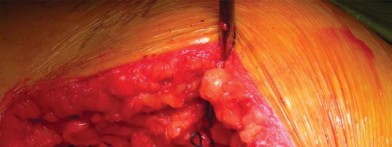

إدارة الأنسجة الرخوة وخلع رأس الفخذ

تُشق اللفافة العريضة والألياف الأمامية للعضلة الألوية الكبرى التي تتصل باللفافة العريضة قريبًا باستخدام الكي الكهربائي بما يتماشى مع شق الجلد. يتم إزاحة الجراب المدوري خلفيًا للمساعدة في رؤية العضلة الألوية الوسطى والعضلة المتسعة الجانبية. يتم رفع الجزء الأمامي من العضلة الألوية الوسطى عن المدور الكبير باستخدام الكي الكهربائي، ثم يتم تشريحه بشكل غير حاد بما يتماشى مع أليافه بزاوية 45 درجة أمامية-قريبة عند تقاطع الثلثين الأوسط والأمامي للعضلة. يقتصر التشريح على أقل من 3-4 سم باتجاه الرأس من طرف المدور الكبير لتجنب إصابة العصب الألوي العلوي. في غلاف مستمر مع العضلة الألوية الوسطى، يتم رفع الجزء الأمامي من العضلة المتسعة الجانبية عن حافة العضلة المتسعة ويتم شقه بعيدًا بين ثلثيه الأوسط والأمامي. يتم وضع مبعد هومان غير حاد في شق العضلة الألوية الوسطى لسحب الألياف الخلفية وكشف طبقة من الدهون بين المستويات الألوية. تُشق الكبسولة خلف العضلة الألوية الصغرى وعلى طول الجانب العلوي من عنق الفخذ. يقوم المساعد بتباعد وثني وتدوير الطرف خارجيًا لخلع رأس الفخذ.

تحضير الفخذ والحق